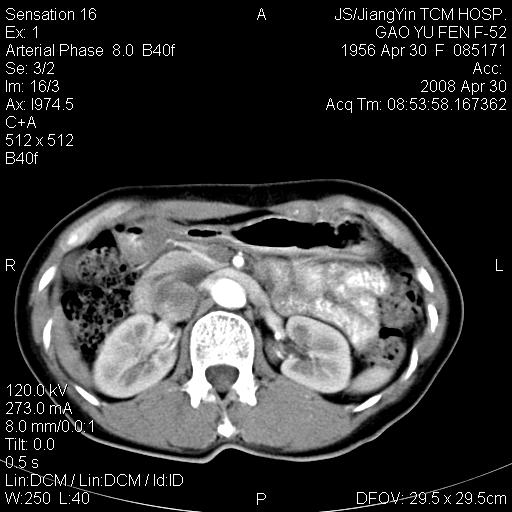

标题: CT13307:肠系膜囊肿? [打印本页]

标题: CT13307:肠系膜囊肿?

囊性淋巴管瘤可能比较大。

良性囊性占位,来源于肠系膜的可能性大

病变位于肾静脉后方,支持腹膜后占位性病变,以囊性淋巴管瘤可能性大.